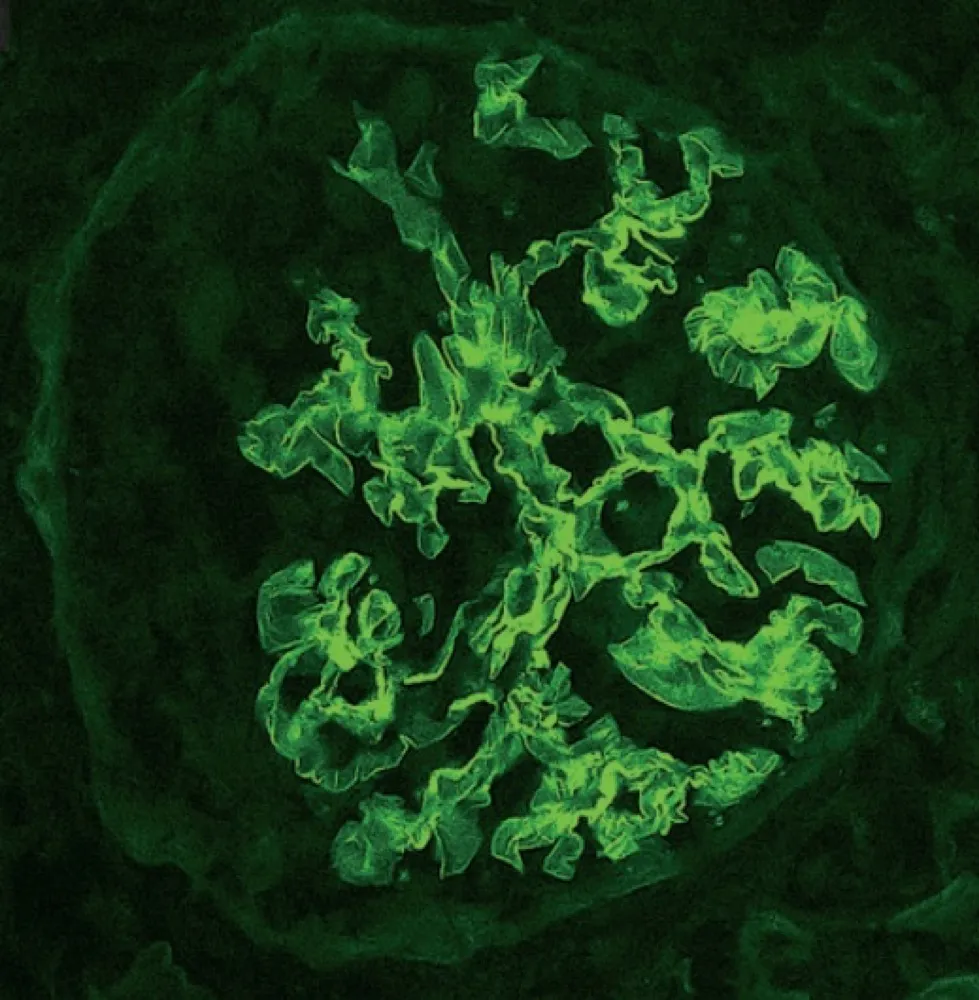

A glomerulonefrite por C3 (GNC3) resulta de ativação descontrolada da via alternativa do complemento e pode simular uma GN pós-infecciosa. O diagnóstico correto depende do reconhecimento do padrão de deposição de C3 e da investigação genética. Com terapias-alvo como o eculizumabe e o iptacopan, identificar precocemente a GNC3 pode mudar o desfecho do paciente.

Luís Sette

9 meses atrás